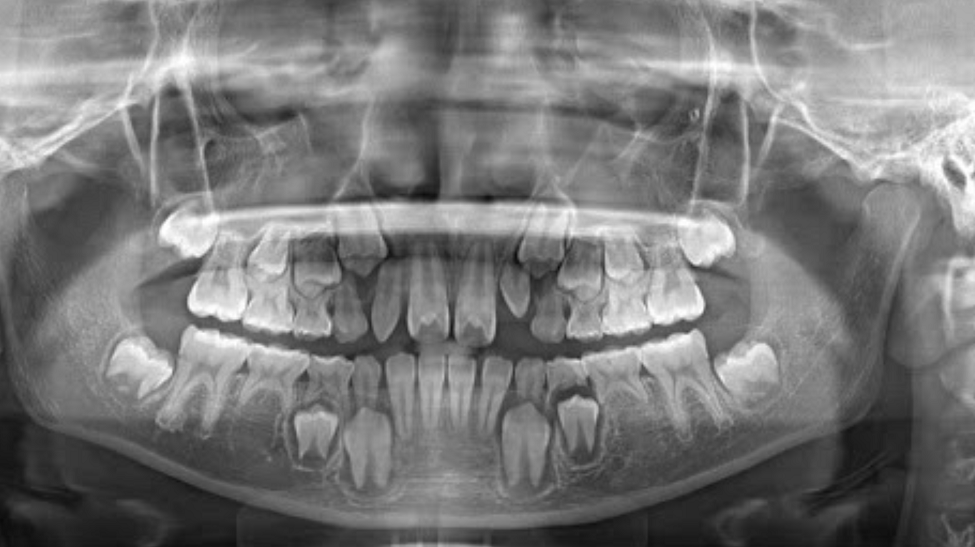

(Mầm răng thực tế là một chiếc răng hoàn thiện nằm trong xương hàm và chờ tới thời điểm để mọc lên)(**)

| Vị trí | Phát triển trong xương hàm, ngay dưới nướu | Nằm sâu hơn trong xương hàm, bên dưới mầm răng sữa |

Trẻ hoàn toàn không có mầm răng trong xương hàm